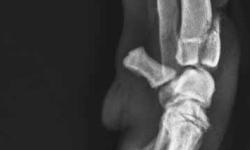

Pacient č.: 1. - rtg zranění.

Pacient č.: 2. - rtg před operaci, hypertenze karpu.

Pacient č. 3. - předoperační rtg.